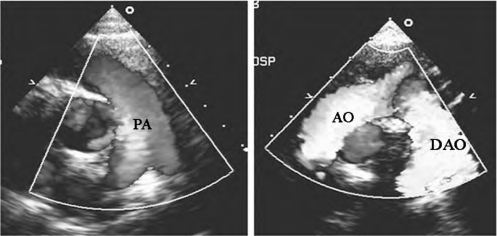

图10-30 肺动脉瓣口和主动脉腔内彩色多普勒血流图(见彩图8)

左图:大血管短轴切面,收缩期蓝色血流束经肺动脉瓣口进入主肺动脉腔内;右图:胸骨上凹主动脉弓长轴切面,显示升主动脉及降主动脉内血流